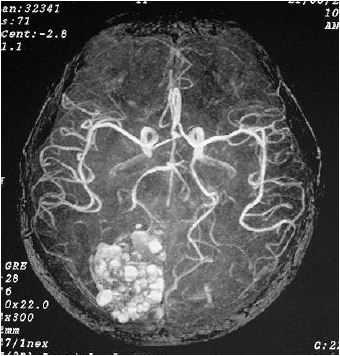

O efeito em massa apresentado demonstra compressão no corno